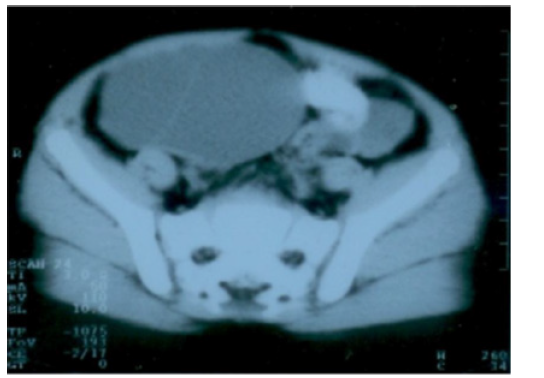

Auto antibodies and anti Tg against thyroid gland were negative. Thyroid ultrasound showed absence of thyroid gland in normal location. Scintigraphy with Technetium 99 showed light isotope uptake in the sublingual region and absence of isotope uptake in the normal thyroid position. Abdominal and pelvic ultrasound showed: Adult size uterus 66x34x24 mm and endometrial thickness 6 mm. Right ovary was enlarged with a cyst measuring 83x61mm, left ovary was enlarge measuring 38x26 mm. Liver, spleen, pancreas, both kidneys were within normal range. CT scan showed enlargement of both ovaries with a mass in the right one. Pituitary Magnetic Resonance Imaging (MRI) showed homogenous generalized enlargement of the pituitary gland.

The bilaterally enlarged (Figure 1A) (Figure 1B) (Figure 1C) and multicystic ovaries were suggestive of ovarian hyperstimulation rather than of autonomous endocrine ovarian activity as seen in secreting ovarian tumors. Very high levels of TSH seen in profound hypothyroidism interact with FSH receptor inducing FSH-like effects on gonads in the absence of LH effects, a phenomenon called “specificity spillover” because TSH and FSH, along with (LH) and Human Chorionic Gonadotropin (HCG), share a common beta subunit. It is theorized that in large amounts, TSH can activate the FSH receptor secondary to this common subunit. This stimulates ovaries resulting in polycystic ovaries, uterine bleeding and breast enlargement in girls without increase in androgens. This explains also the absence of axillary and pubic hair [2, 4]. Also, in this case the child didn’t have axillary or pubic hair.